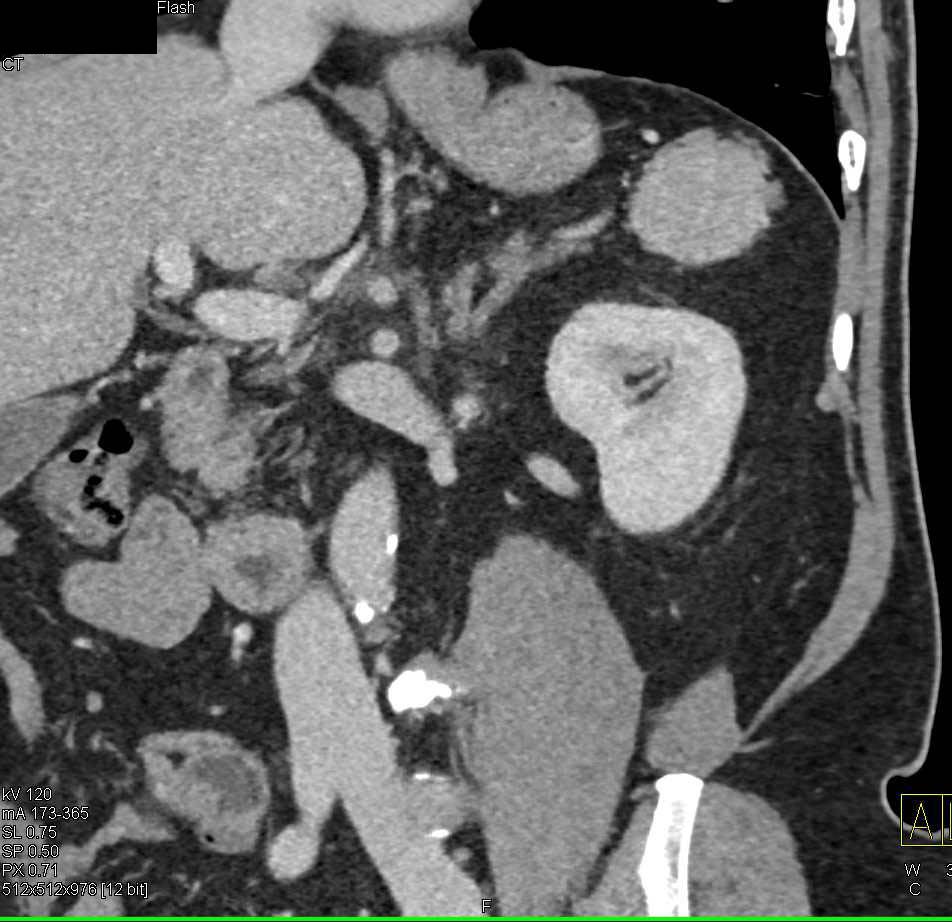

How are accessory spleens diagnosed?

Accessory spleens are often discovered incidentally during imaging studies, such as ultrasounds or CT scans, performed for other reasons.